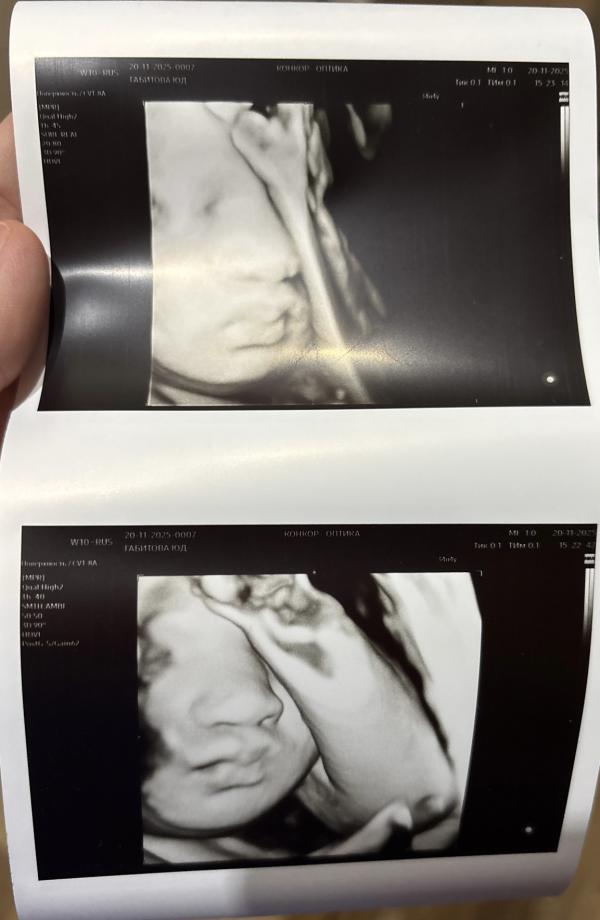

Сегодня прошла 3 скрининг. По узи все хорошо, весим 2309🥹обвития нет, положение правильное 🤞

Врач сказала, что ребенок волосатенький и реснички даже длинные, она удивилась прям, потому что такое редко видно на узи 😅